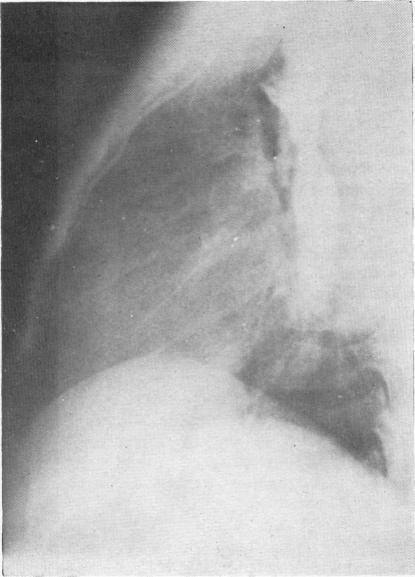

LATE RESULTS OF THE OPERATION FOR COARCTATION IN THE GROWING CHILD.

Arch Dis Child. 1965 Apr;40(210):192-6. doi: 10.1136/adc.40.210.192.